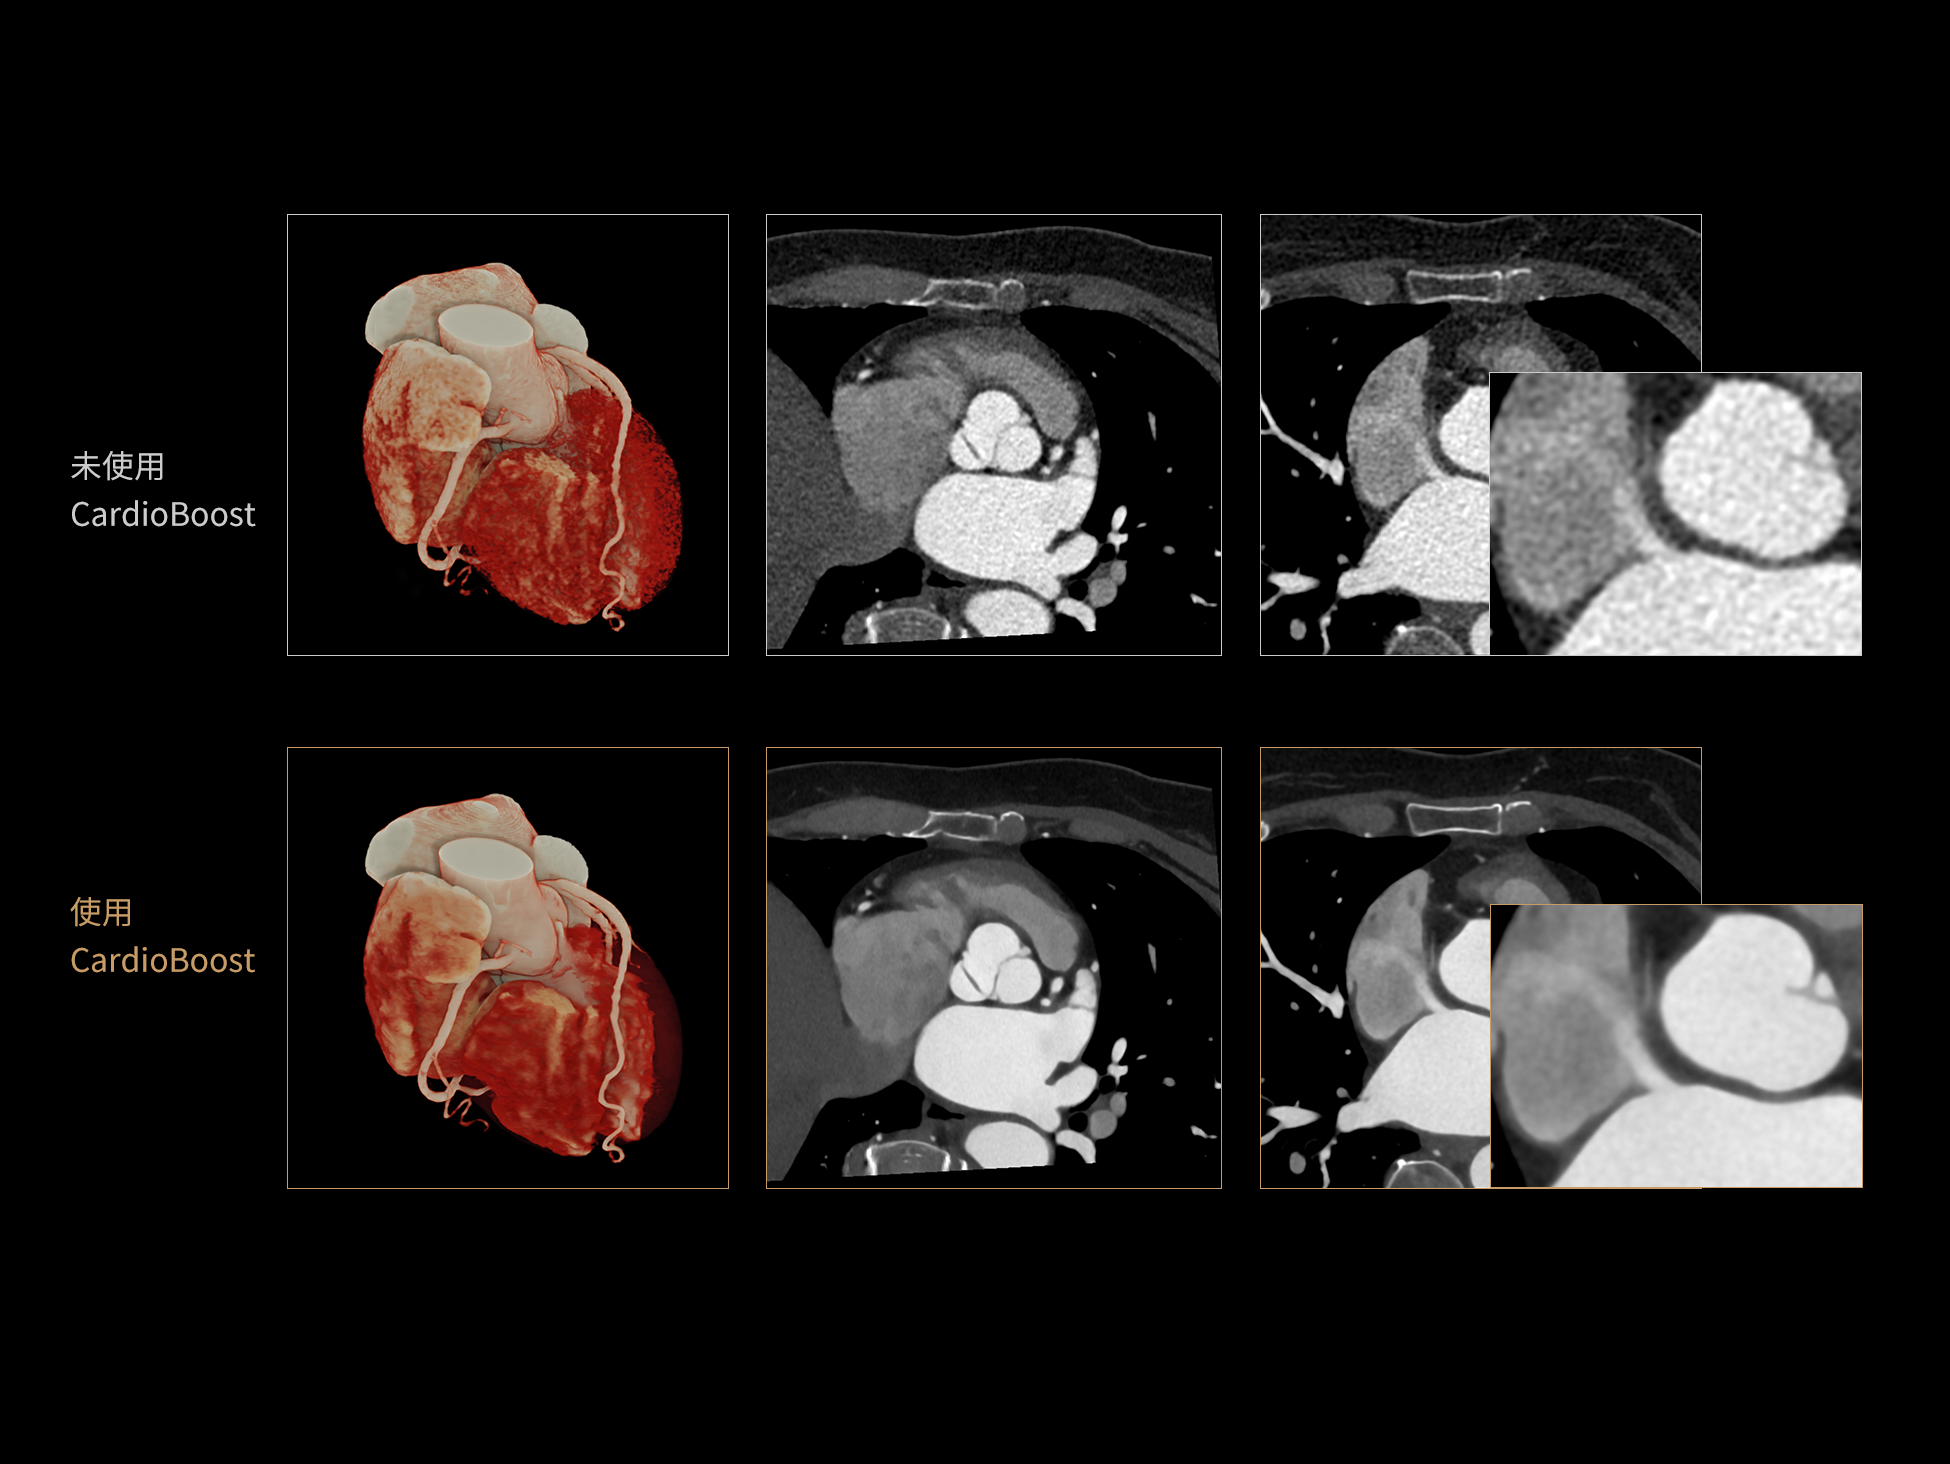

CardioBoost:专属网络设计,重塑心脏影像表现

目前心脏的 CT 检查还存在辐射剂量偏高、空间分辨率不足、 致密钙化伪影影响冠脉狭窄程度评估等方面的限 制[1][2]。CardioBoost 技术专为心脏 CT 高清成像而开发,通过 3D 神经网络的深度学习技术,利用先进的注意力机制在识别关键成像特征方面的出色表现,能够精确地聚焦于斑块、支架以及微小血管等关键细节,清晰展示这些结构与冠脉血管的边界,从而显著提高诊断的准确性,并提升医生的诊断信心。创新的 CardioBoost 心脏图像重建算法,不仅实现了图像清晰度的提升和伪影的去除,更能在减少辐射剂量的同时,保证心脏图像的高质量和图像纹理的自然。

CardioBoost核心创新

采用 3D 神经网络的空间结构优势与精细的组织分类能力,CardioBoost 技术优化了组织对比,高清展示血管斑块,使斑块与血管边缘的轮廓清晰可辨,提升斑块诊断与评估的精确性。

借助 3D 神经网络设计、空间注意力机制聚焦与特征强化作用,CardioBoost技术提升图像的空间分辨率,实现冠脉支架的高清成像,对支架形态与管腔通畅度的评估更精准。

CardioBoost 整合先进的 3D 神经网络和空间注意力机制,大幅增强数据处理的速度与精确度。该技术能有效抑制由致密钙化引起的晕状伪影,清晰展现钙化斑块的原始结构和大小,对冠脉狭窄的评估更加精确可靠。